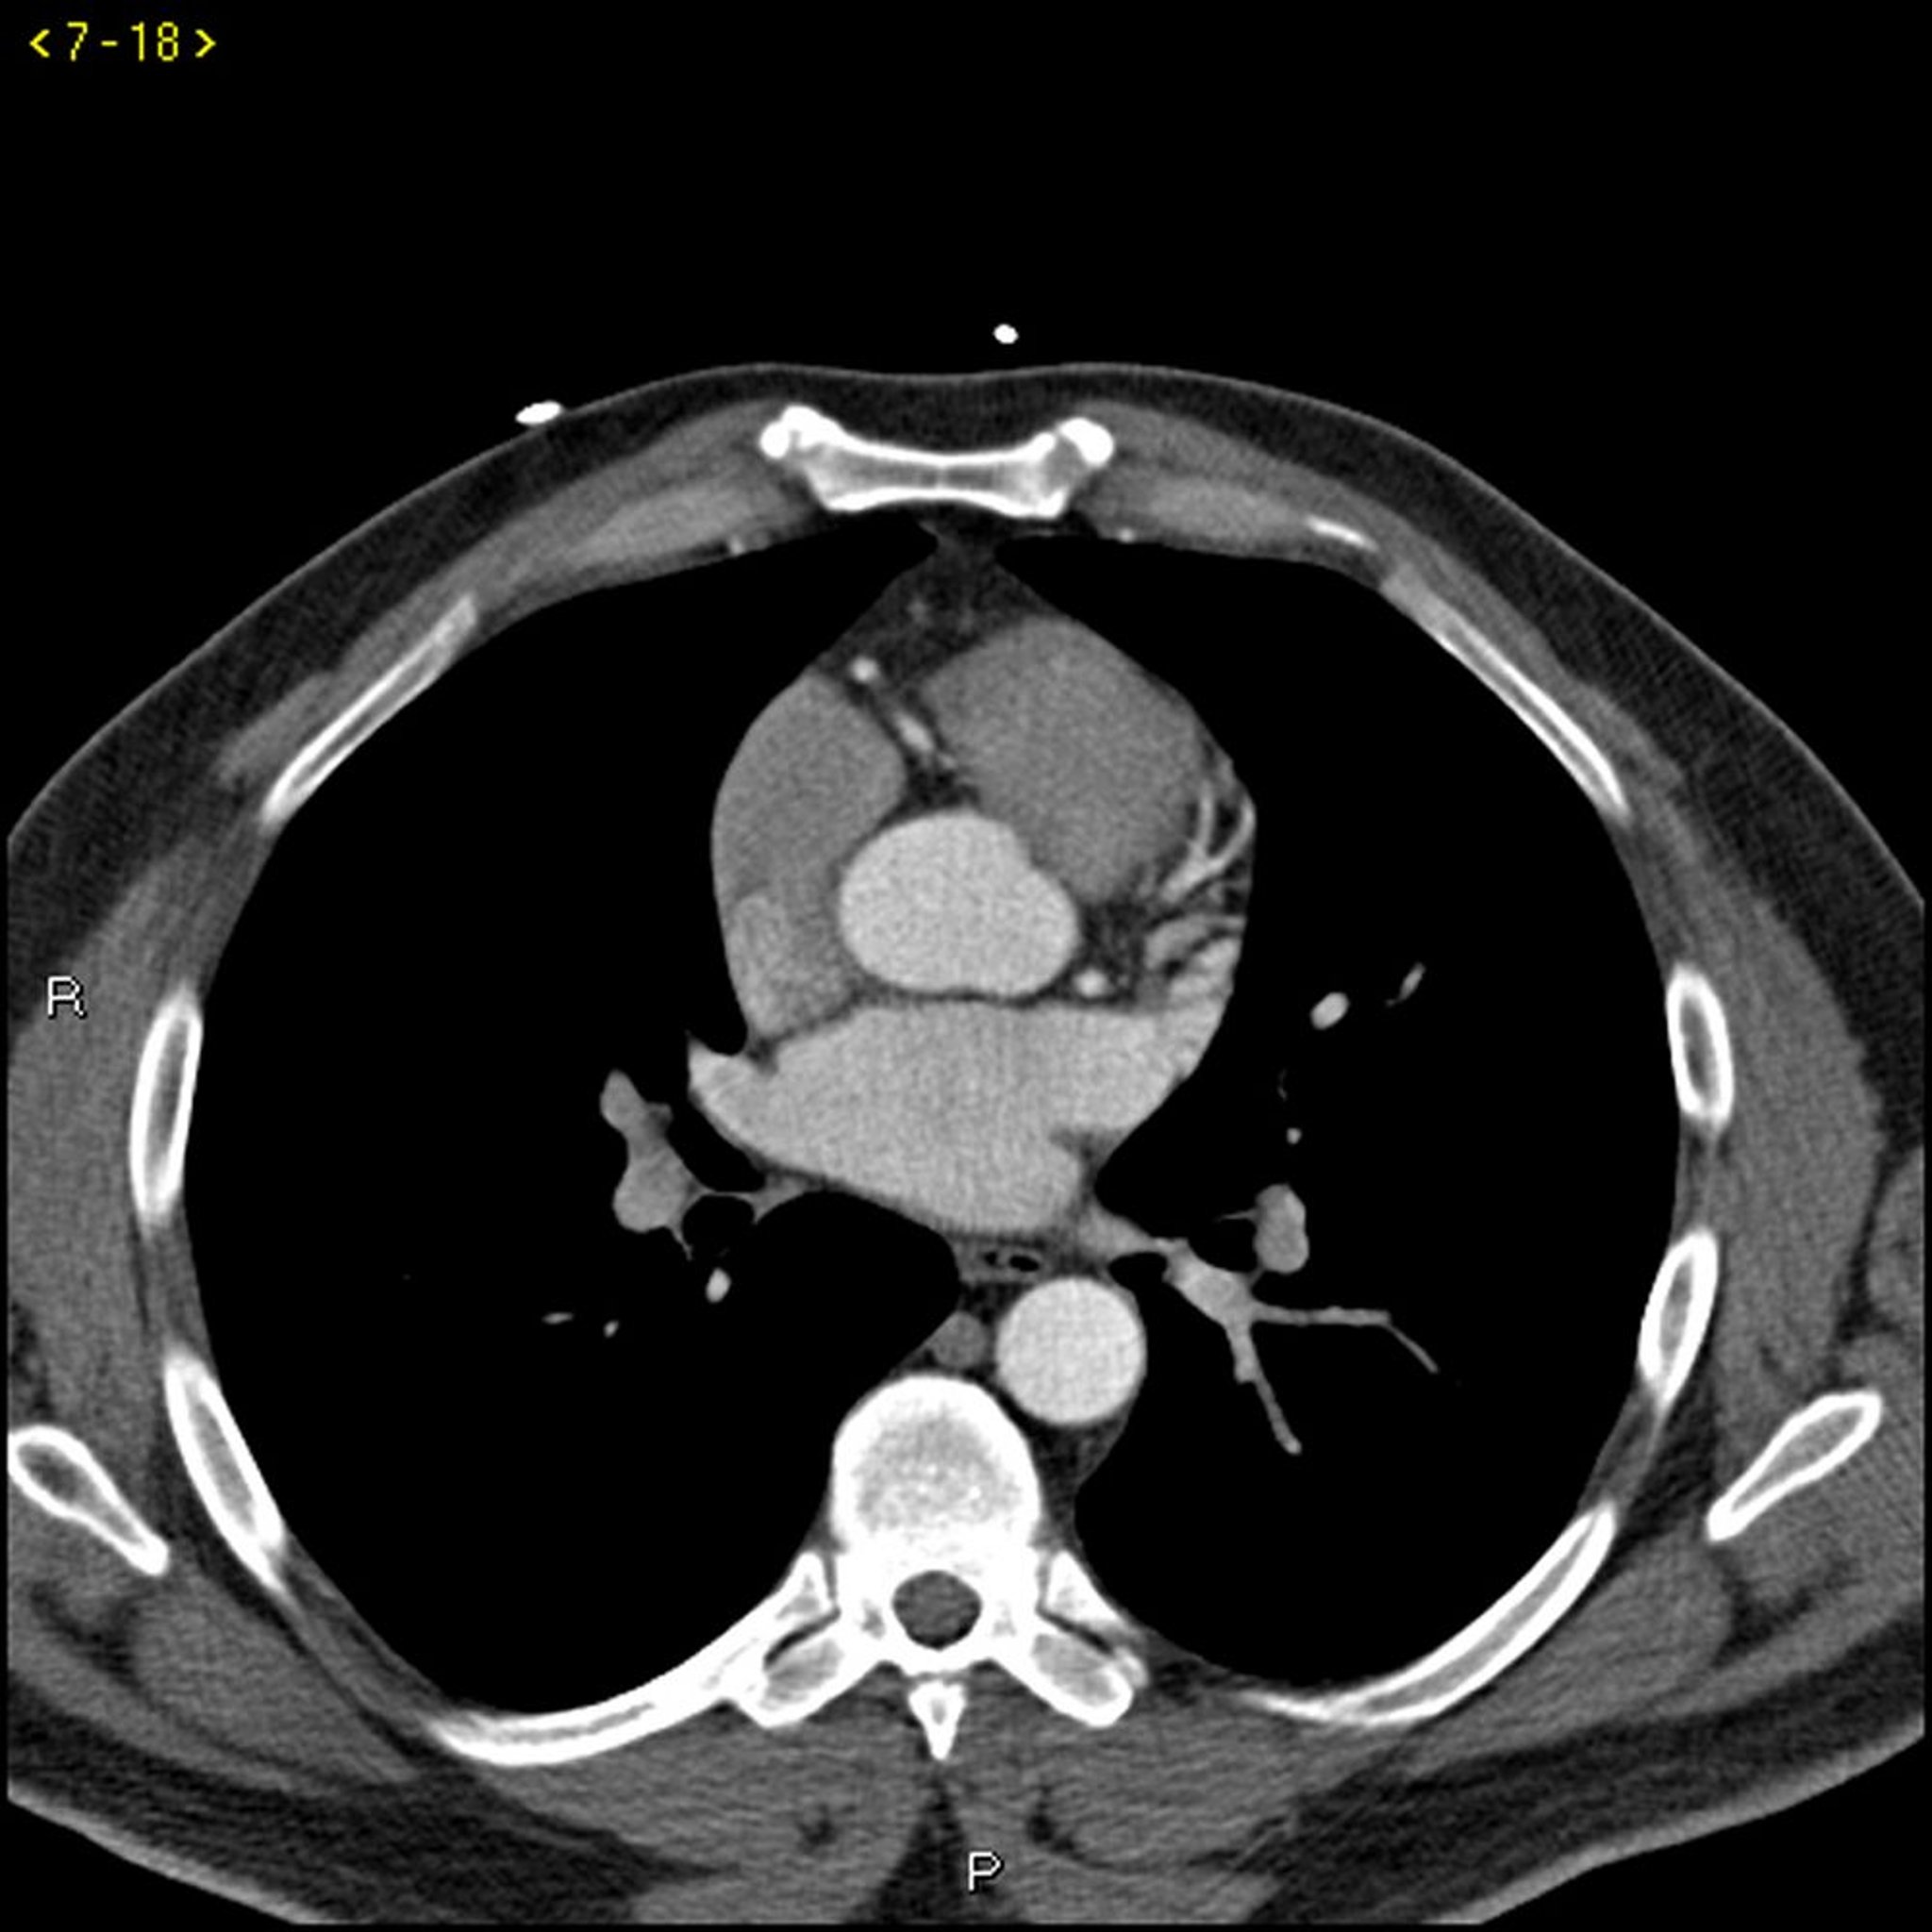

TC con contrasto che mostra arterie coronarie normali, slide 3

Questa TC con contrasto mostra arterie coronarie normali. L'arteria coronaria principale sinistra è indicata dalla freccia rossa. Le arterie discendente anteriore sinistra e circonflessa sinistra sono indicate rispettivamente dalle frecce verde e blu e l'arteria coronaria destra è indicata dalla freccia viola.